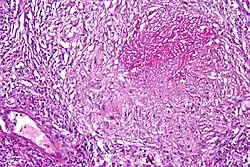

Lab findings

Distinctive clusters of colorless Mycobacterium tuberculosis form in this culture.

A definitive diagnosis of tuberculosis can only be made by culturing Mycobacterium tuberculosis organisms from a specimen taken from the patient (most often sputum, but may also include pus, CSF, biopsied tissue, etc.).[1] A diagnosis made other than by culture may only be classified as "probable" or "presumed". For a diagnosis negating the possibility of tuberculosis infection, most protocols require that two separate cultures both test negative.[1]

Culture

Many types of microbiological culture are available.[12] Traditionally, cultures have used the Löwenstein-Jensen (LJ), Kirchner, or Middlebrook media (7H9, 7H10, and 7H11). A culture of the AFB can distinguish the various forms of mycobacteria, although results from this may take four to eight weeks for a conclusive answer. New automated systems that are faster include the MB/BacT, BACTEC 9000, VersaTREK, and the Mycobacterial Growth Indicator Tube (MGIT). The Microscopic Observation Drug Susceptibility assay culture may be a faster and more accurate method.[13]